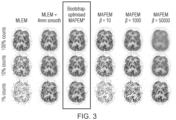

- Figure 1 comprises a low, mid- and high-count data comparison (for 1%, 10% and 100% of the measured real data).

- the first column comprises the conventional MLEM reconstruction of these three cases, the second column shows these images with typical post-smoothing with a 4 mm Gaussian kernel (as often done as standard for clinical images).

- the rightmost three columns (columns 4, 5 and 6) show standard MAPEM reconstructions for different choices of the hyperparameter ⁇ , where it can be seen that the visually better results are obtained for different choices of hyperparameter for different count levels.

- the third column outlined in the Figure, shows that the bootstrap-optimised MAPEM method automatically delivers images of good quality for all count levels, which cannot be found using the other methods unless their hyperparameters are adjusted and explored by the user.

- Figure 3 comprises a similar comparison to that of Figure 1 , the general structure of columns and images is the same as that described in relation to Figure 1 , but now making using the MR image from Figure 2 , in order to provide prior structural information for MAP EM to assist in the noise compensation, using the Bowsher method [2].

- the bootstrap-optimised MAPEM method automatically picks the appropriate hyperparameters for all noise levels. It will be appreciated that the level of noise compensation applied by implementations described above is appropriate to the level of noise in the data. It is believed that a clinician would prefer images such as those shown in the third outlined column, compared to the current standard methods shown in the other columns.

- Figures 1 and 3 illustrate possible results using implementations in accordance with described approaches, with high count data and extremely low count data, and the same algorithm has been used in both cases. It can be seen that consistent good quality images are obtained by applying a method in accordance with described approaches.

- the third outlined column shows an excellent result in which a strength of smoothing, the amount of the prior which is used, is visually appropriate.